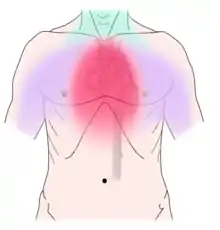

Discomfort caused by coronary artery disease can radiate to the neck, lower jaw and teeth

Non-dental causes of toothache are much less common as compared with dental causes. In a toothache of neurovascular origin, pain is reported in the teeth in conjunction with a migraine. Local and distant structures (such as ear, brain, carotid artery, or heart) can also refer pain to the teeth.[35]:80,81 Other non-dental causes of toothache include myofascial pain (muscle pain) and angina pectoris (which classically refers pain to the lower jaw). Very rarely, toothache can be psychogenic in origin.[10]:57–58

Disorders of the maxillary sinus can be referred to the upper back teeth. The posterior, middle and anterior superior alveolar nerves are all closely associated with the lining of the sinus. The bone between the floor of the maxillary sinus and the roots of the upper back teeth is very thin, and frequently the apices of these teeth disrupt the contour of the sinus floor. Consequently, acute or chronic maxillary sinusitis can be perceived as maxillary toothache,[36] and neoplasms of the sinus (such as adenoid cystic carcinoma)[37]:390 can cause similarly perceived toothache if malignant invasion of the superior alveolar nerves occurs.[38]:72 Classically, sinusitis pain increases upon Valsalva maneuvers or tilting the head forward.[39]